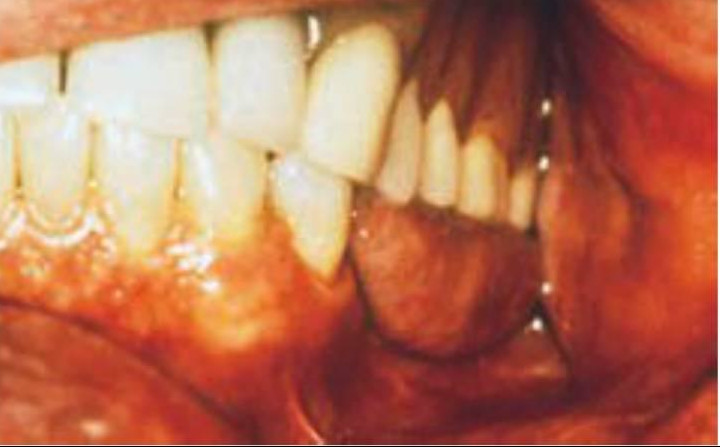

Un signo clínico típico del apretamiento es el borde festoneado de la lengua (fig. 6-13).

Normalmente, la lengua se apoya contra las superficies linguales de los dientes maxilares al apretar, ejerciendo una presión lateral que da como resultado el borde festoneado. Esta posición de presión de la lengua se puede acompañar también con un vacío intraoral, lo que permite que el apretamiento se prolongue durante más tiempo, a menudo mientras se duerme.